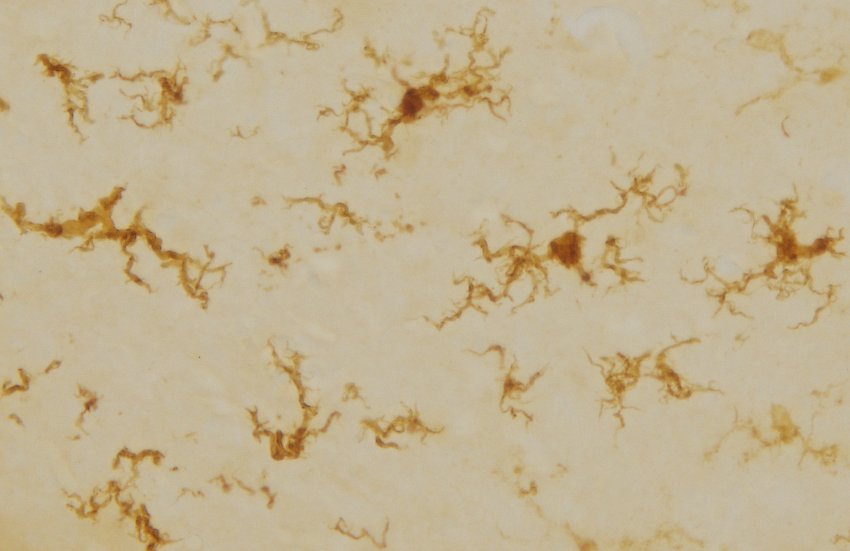

Un'immagine ingrandita delle microglia rigenerate. Hanno una forma simile a quella 'attivata' tipica di quando affrontano l'infiammazione. (Foto: Alita Soch)

È importante sottolineare che le microglia rigenerate avevano una forma diversa, simile alla forma 'attivata' che queste cellule hanno quando affrontano l'infiammazione. Ancora la Spencer:

“Stiamo ancora esplorando ciò che rende diverse queste cellule quando ripopolano il cervello, ma la loro forma ci dice che possono essere più attive del solito, rendendo potenzialmente più efficaci i neuroni a favorire una memoria migliore.